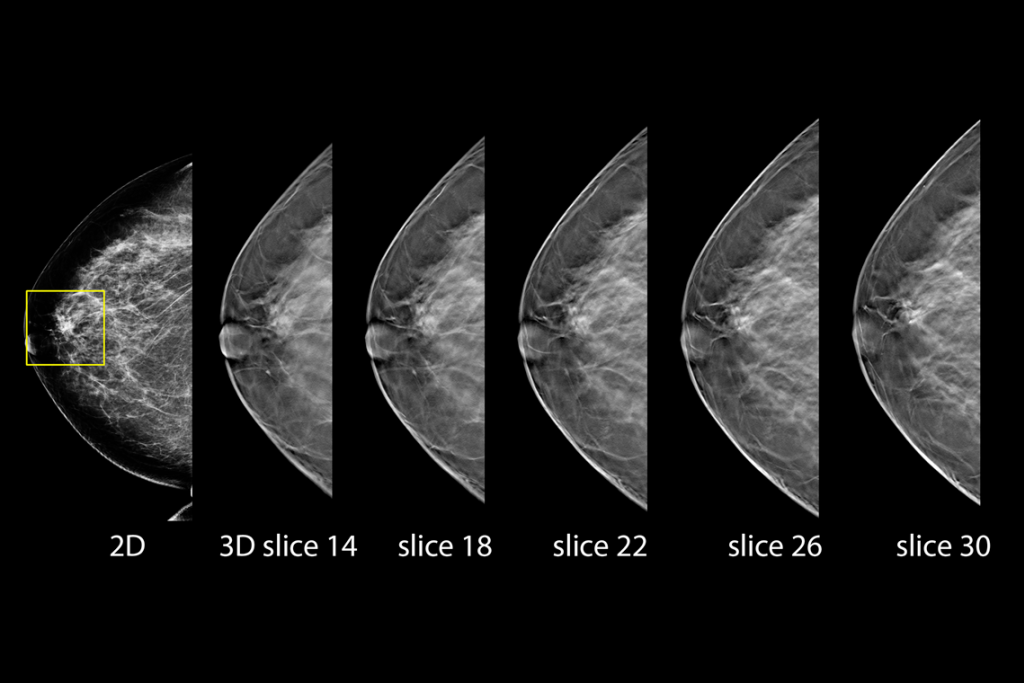

Clinical images of breast scan mammography

Clinical images of breast scan

Clinical images of breast scan with fatty breast